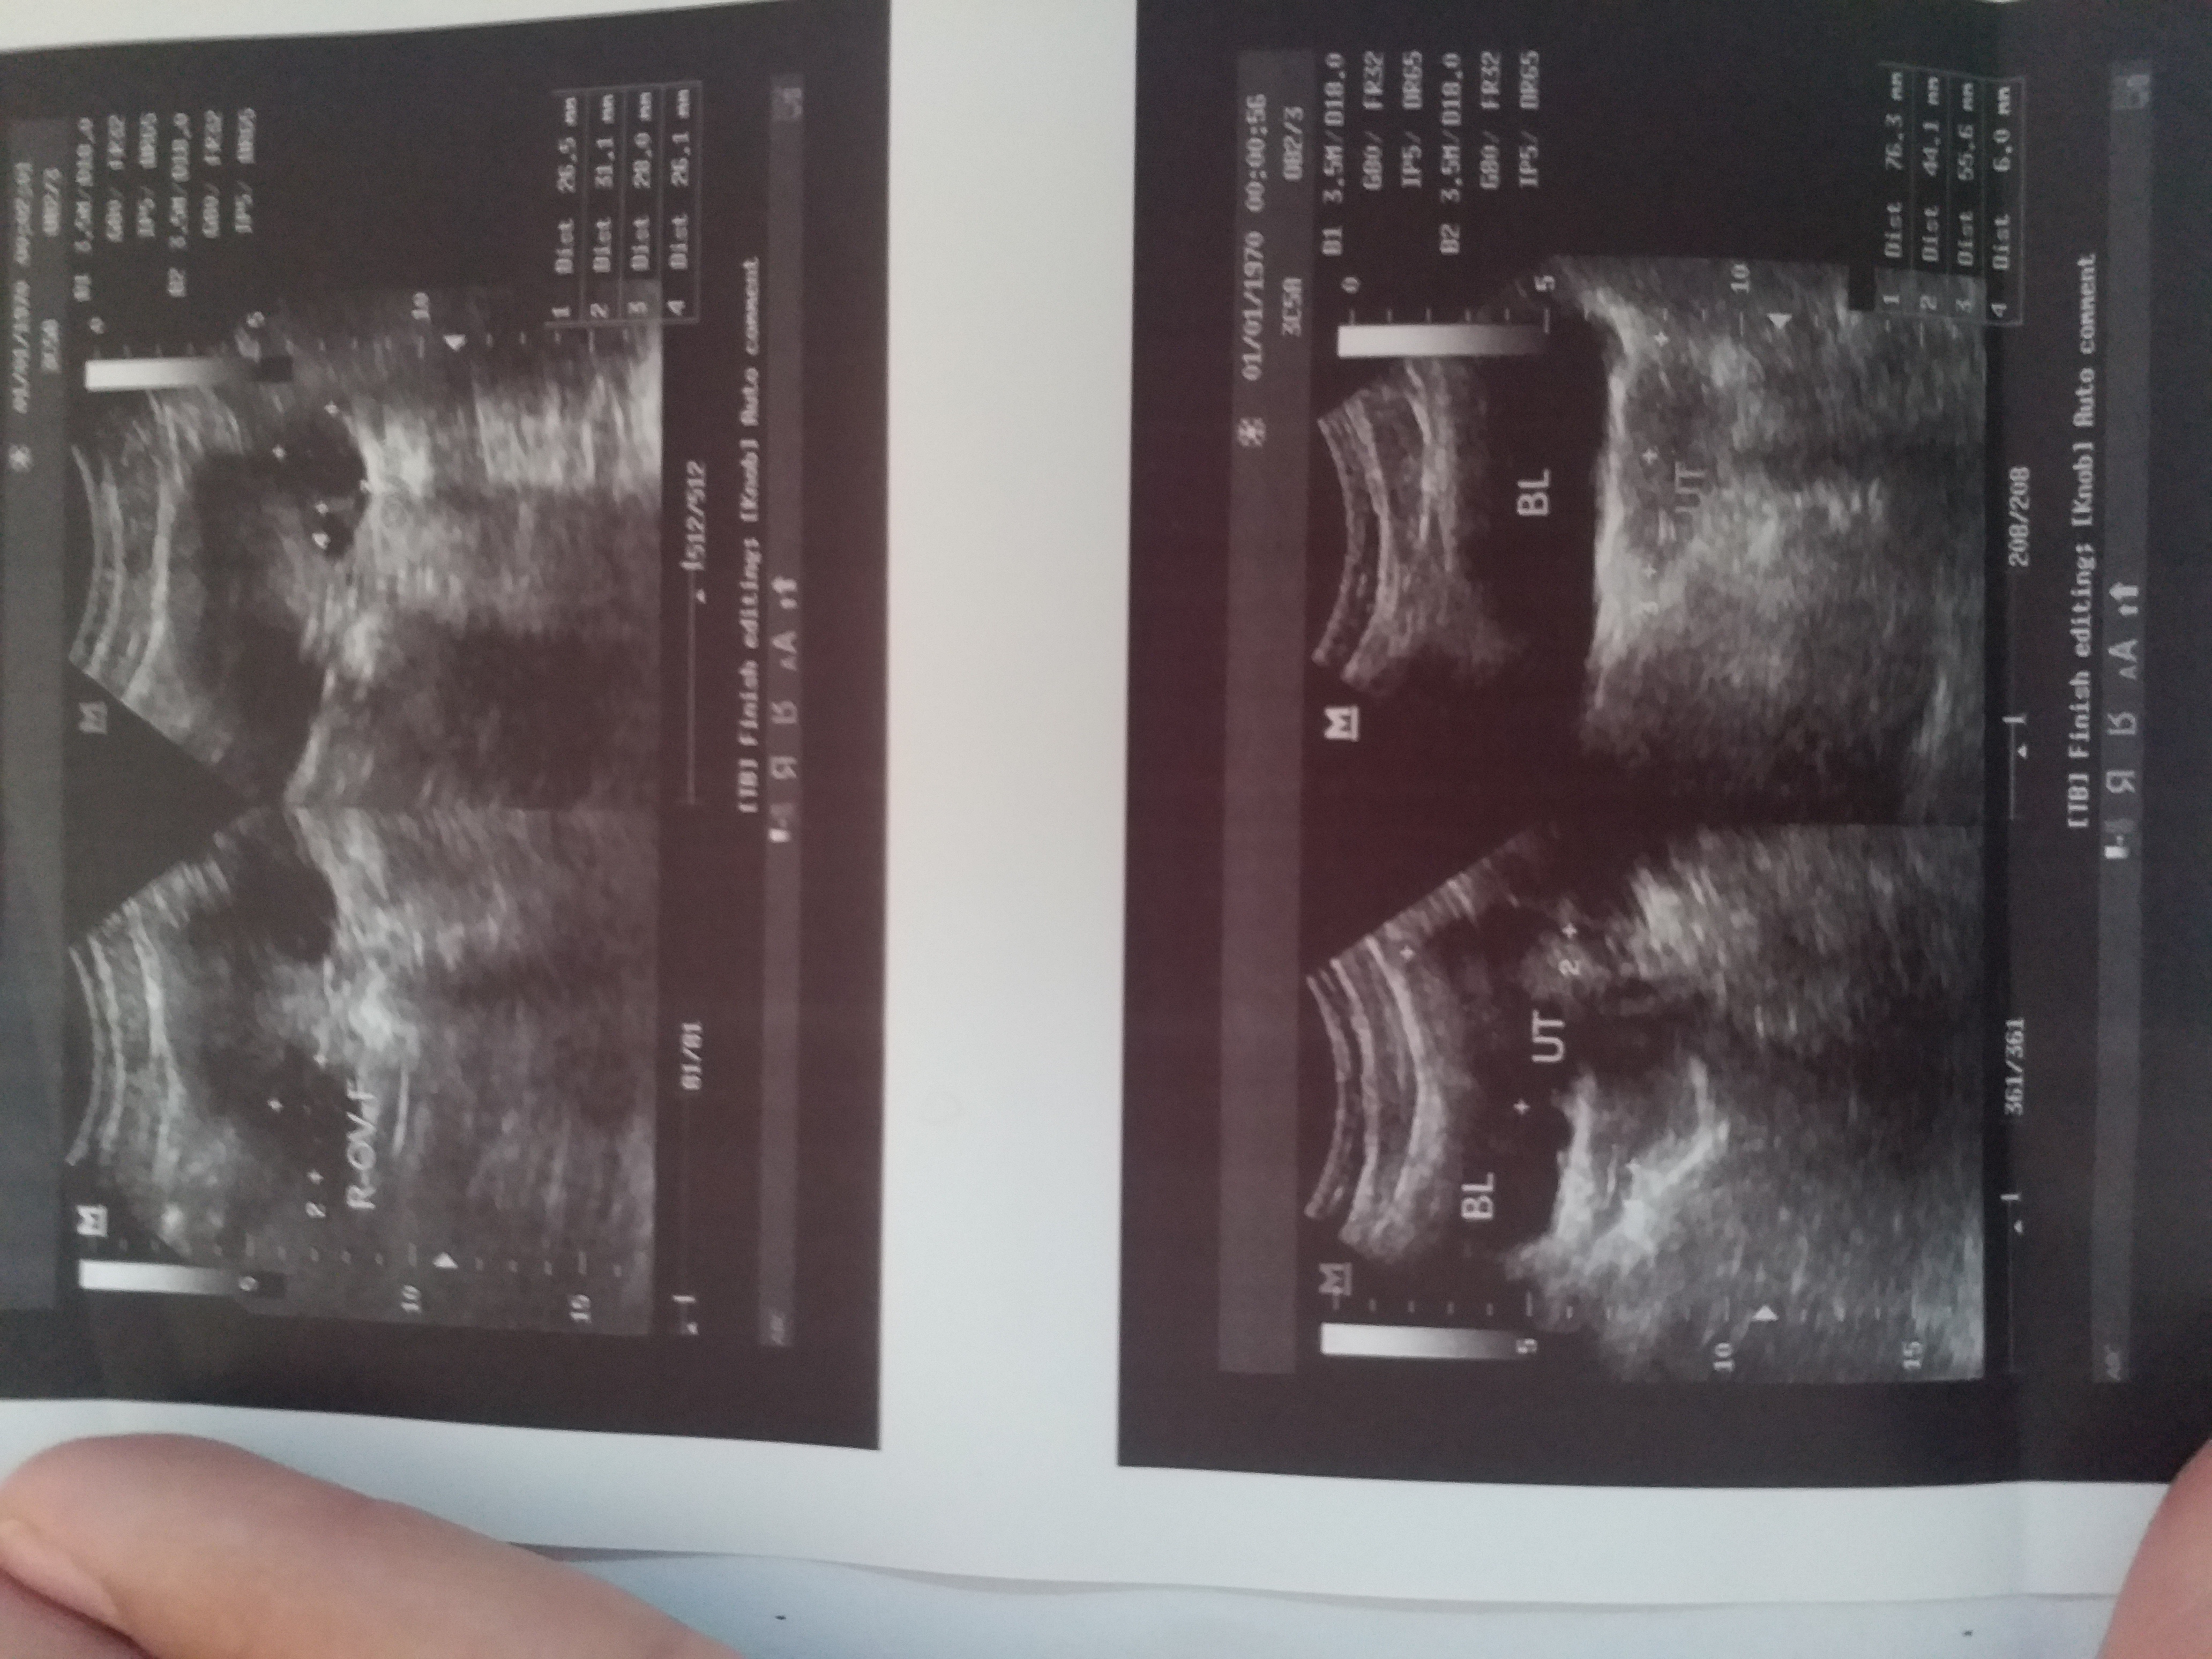

خیلی بزرگن فولیکول هات، آمپول نداد دکتر که زودتر آزاد بشن!؟

بهتره بین 18 تا 24 باشه